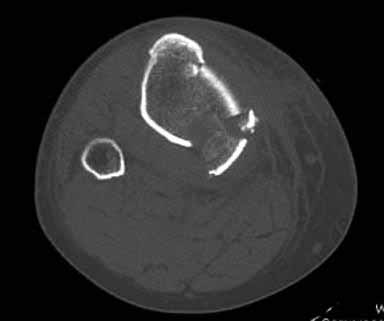

На снимке типичный перелом медиального тибиал плато с передним смещением (подвывих) по Schatzker IV. Консервативное лечение без медиальной опоры не может удержать деформирующие силы, и из-за вторичного смещения мыщелка конечность смещается в варус. Кроме передних смещений еще встречаются сложные фронтальные варианты переломов, и тогда голень подвывихивается кпереди.

А в данном случае мыщелок сросся со смещением кпереди и ротирован. За счет интактной наружной колонны опороспособность конечности сохранена, но остается варус и экстензия конечности. Для предоперационного расчета необходимо сделать на всю длину конечности рентгенограмму, а в остром периоде КТ и 3-мерный снимок помогут лучше ориентироваться в характере перелома.

Остеотомия с разворотом медиального мыщелка, и для фиксации можно применить параллельные субхондральные межмыщелковые шурупы. Дополнительная медиальная Smith-Nephew PERI-LOC™ (Periarticular Locked Plating System) пластина. При отсутствии специальной пластины можно адаптировать Tomofix для высокой остеотомии. Доступ прямой медиальный через pes anserinus или через интервал pes с medial gastrocnemeus.